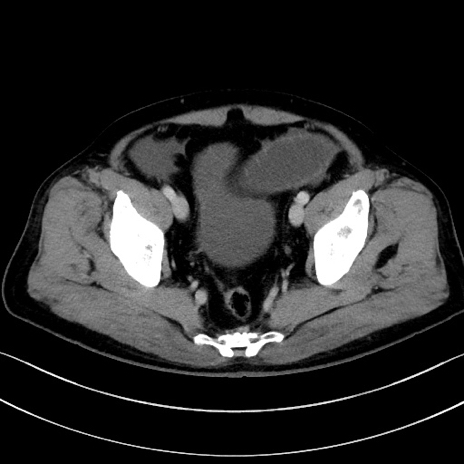

症例15(横断像)

症例

【症例】70歳代男性

【主訴】腹痛

【現病歴】今朝から腹痛あり。全体的に痛い。特に左上の方。排ガスが今日はない。冷や汗が出る。

【既往歴】直腸癌術後

【身体所見】左側腹部〜上腹部に圧痛あり。腹膜刺激症状明らかなではない。軽度反跳痛。左下腹部に術後瘢痕あり。

【データ】WBC 7700、CRP 0.02